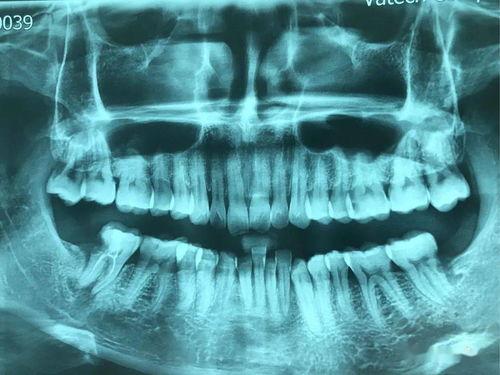

在牙科診斷中,影像學檢查是不可或缺的工具??谇蝗癤光片和口腔CT是兩種常見的檢查方法,它們?yōu)獒t(yī)生提供了重要的診斷依據(jù)。然而,很多患者對這兩種檢查方式的區(qū)別并不清楚。本文將詳細介紹口腔全景X光片和口腔CT的差異,幫助您更好地了解這兩種檢查手段。

口腔全景X光片是通過X射線在一個平面上對口腔進行掃描,從而獲得一張包含上下頜骨、牙齒及周圍組織的全景圖像。它能夠展示牙齒的整體排列、牙槽骨的形態(tài)以及關節(jié)的大致情況。其特點是成像速度快,輻射劑量相對較低,價格較為經(jīng)濟實惠。但由于是二維圖像,存在影像重疊的問題,對于一些復雜的口腔結構可能無法清晰顯示。

主要用于常規(guī)的口腔檢查,如牙齒的萌出情況、牙齒的缺失、齲壞、牙周病的初步評估等。它能夠快速地為醫(yī)生提供一個整體的概覽,但對于細微的病變或深部結構的顯示有限。例如,在診斷多生牙、阻生智齒時,可以初步確定牙齒的位置和方向。

口腔全景X光片和口腔CT區(qū)別

圖像清晰度相對較低,對于一些細微的結構,如牙根的細小分叉、早期的牙槽骨吸收等可能無法清晰顯示。而且由于是平面圖像,對于牙齒和組織的前后重疊部分,難以準確判斷其真實情況。